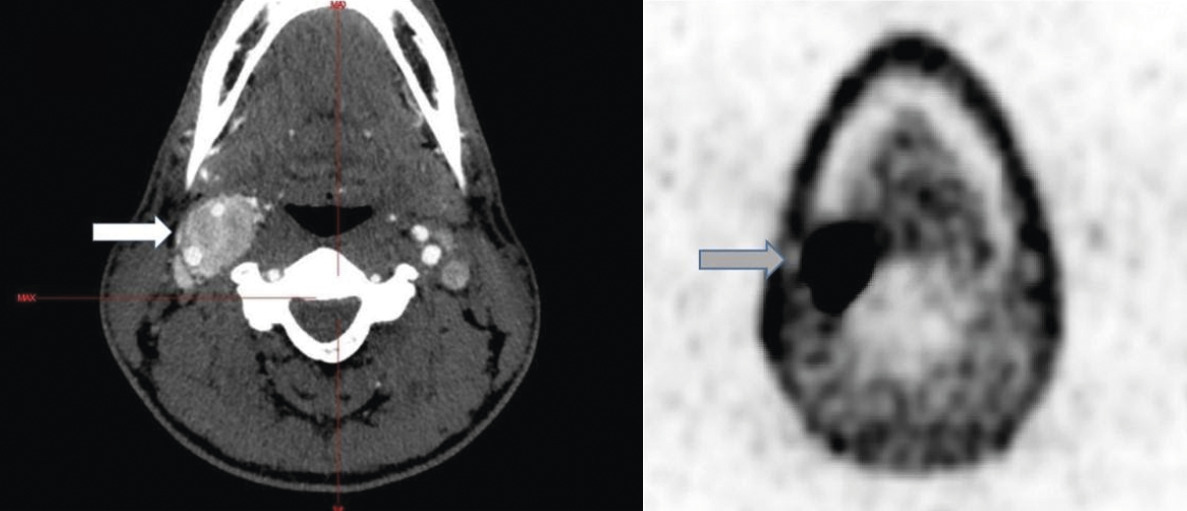

Sur le plan biologique, les dérivés méthoxylés plasmatiques sont normaux (métanéphrine libre plasmatique à 0,17 nmol/L [normale < 0,4] et normétanéphrine libre plasmatique à 0,53 mmol/L [normale < 1,1]). Sur le scanner thoraco-abdomino-pelvien, aucune anomalie n’est décelée, notamment ni lésion hypervasculaire ni atteinte des glandes surrénales. L’imagerie par résonance magnétique (IRM) et l’angio-IRM cervicales objectivent un paragangliome carotidien droit unique de 39 × 23 mm. En TEP-scan à la DOPA, un hypermétabolisme intense est relevé au sein de la lésion, sans autre foyer de fixation suspect (fig. B).